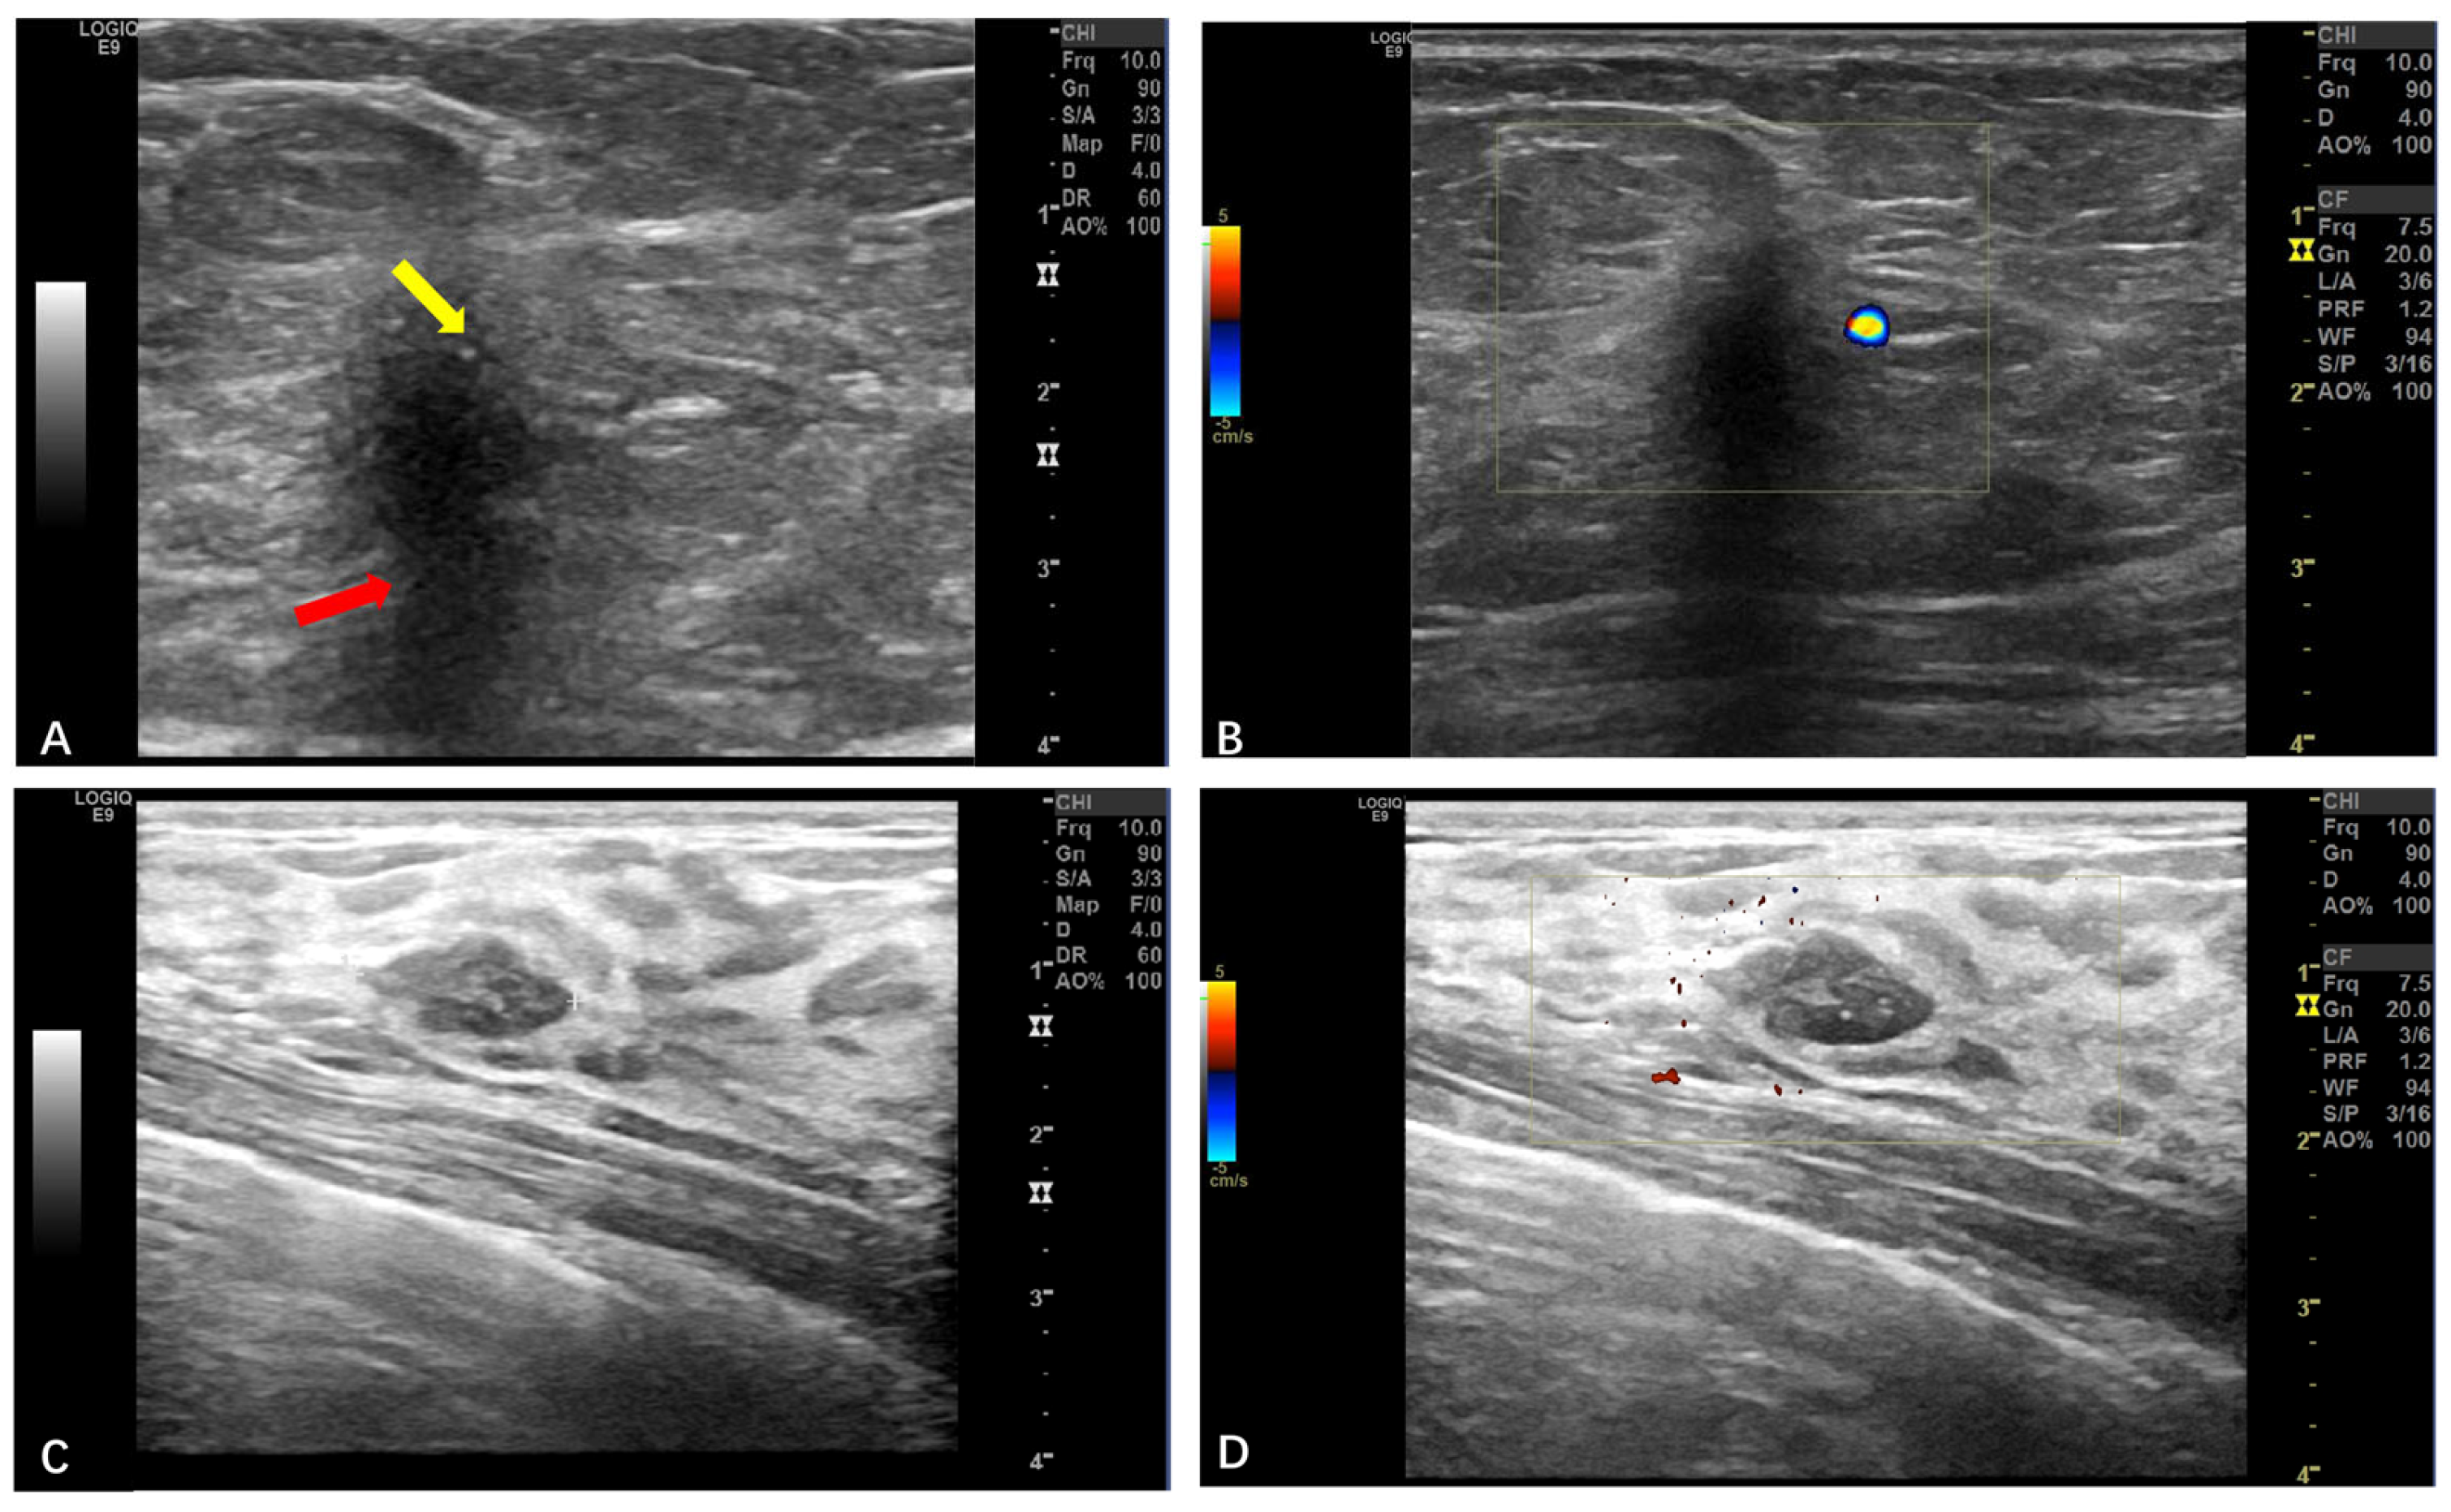

3.2.4. Breast GCTs

| Breasts | Ultrasound (n = 5) | Irregular margins; a non-parallel orientation; posterior shadowing (BI-RADS 4B) (n = 4, 80%) | N/A (all benign) |